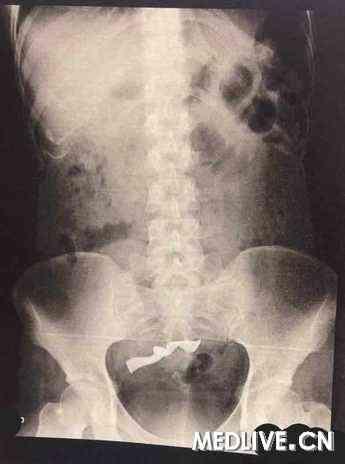

1. 胆囊结石:这是最常见的病因。胆囊结石会导致胆囊发炎,严重时甚至可能引发胆囊癌。为了防止病情恶化,医生会建议切除胆囊。

2. 胆囊炎:胆囊炎也是导致胆囊切除的常见原因。慢性胆囊炎反复发作,会影响生活质量,因此切除胆囊是治疗的最佳选择。

3. 胆囊癌:胆囊癌是一种恶性程度较高的肿瘤,切除胆囊是治疗胆囊癌的重要手段。